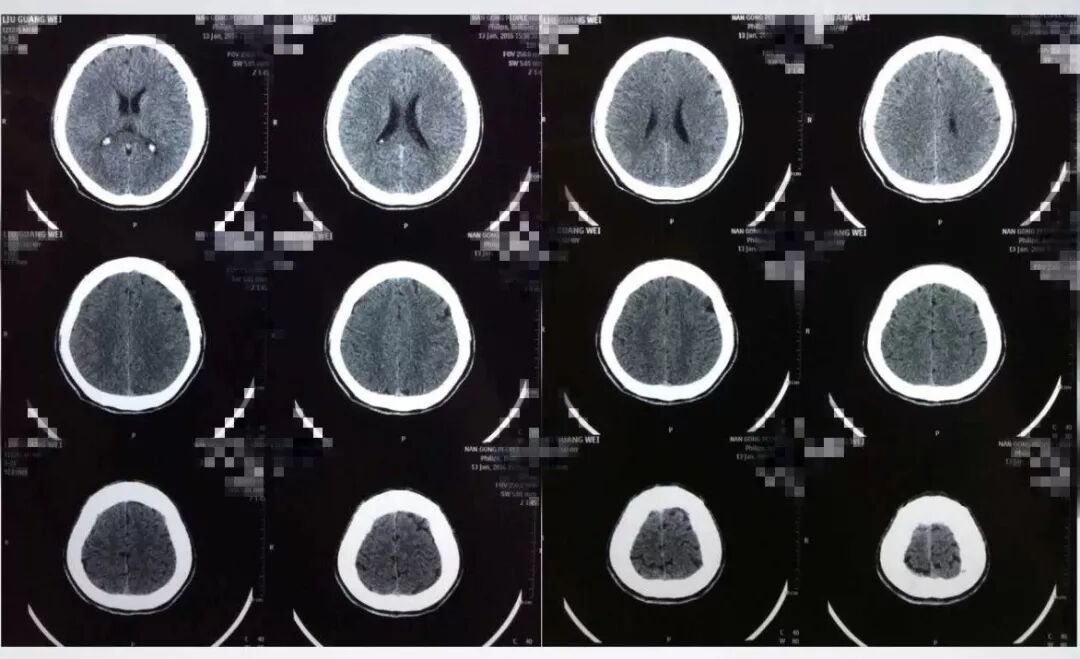

患者缘于10天前无明显诱因突发头痛伴呕吐,于当地医院就诊查头部CT提示:SAH;遂于当地医院予以保守治疗,其后症状逐渐好转;于发病9天后突然出现右眼眼睑下垂及右眼视物不清,遂到河北医科大学第二医院东院区就诊。头部CT提示未见明显出血;头部CTA提示:右侧后交通动脉动脉瘤及左侧脉络膜前动脉动脉瘤。

发病后9天CT